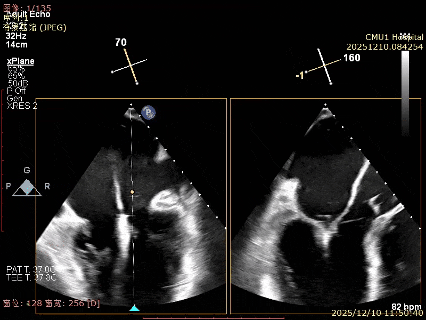

患者食道胃底静脉曲张,遂行TTE术前评估

术前TTE评估:

MR反流病因:DMR(部分腱索断裂)、Carpentier II型;

反流程度:极重度(5+),PISA法估测EROA约1.12cm²,R-VOL约98ml;

病变情况:P2-部分P3,脱垂宽度约27mm ,连枷间距11-13mm,瓣口面积7.8cm²,PML约25mm

其他:TR(重度) ,间接估测PASP约65mmHg;

预估手术难点:后叶冗长,脱垂宽度大,连枷间距大。

为了避免长时间TEE对食道造成损伤,术前即刻3D-TEE短时进一步明确二尖瓣病变相关解剖情况。

术前Bi-com

术前3D

3D-TEE二尖瓣相关解剖学参数:后叶长度:22-25mm,前叶长度:31-34mm;瓣环AP径:47mm,ML径:48mm;瓣口面积:约7.8cm²;脱垂宽度:30mm,最大连枷间距:14mm。

四条肺静脉均可测及收缩期反向血流

术前即刻TEE进一步明确了二尖瓣反流的机制(DMR)及反流程度(5+),重点完善了病变区域二尖瓣解剖结构的评估,预估手术难点/影响手术效果的解剖结构为冗长的二尖瓣后叶(PML约25mm),宽大的脱垂(Flail Width约30mm),超大的连枷间距(Flail gap约14mm)。